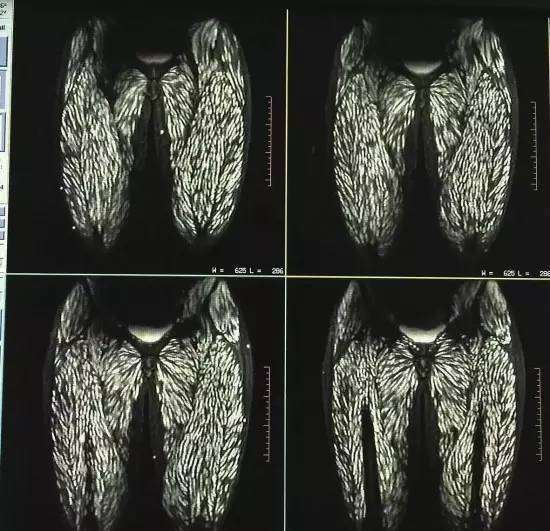

Thật bất ngờ, kết quả xét nghiệm X-quang đã khiến tất cả các nhân viên y tế bị sốc, thậm chí ngay cả đến các bác sĩ đầu ngành lâu năm trong nghề cũng phải ngạc nhiên và giật mình vì kết quả khủng khiếp này. Hoá ra từ màn hình chụp X-quang cho thấy phần sau nhãn cầu, phần đùi, bụng và cơ lưng cùng nhiều nơi khác trên thân thể cô đều bị bao phủ bởi ký sinh trùng. Ngay cả đến lưỡi, phần da mặt đều bị lây nhiễm đến. Sau khi có kết quả kiểm tra máu bác sĩ khẳng định Đình Đình dương tính với sán kháng thể, vì vậy cô đã bị nhiễm bệnh giun sán nặng.

Trên màn hình cho thấy thân thể cô bị bao phủ với những đốm trắng, đó chính là những ký sinh trùng.